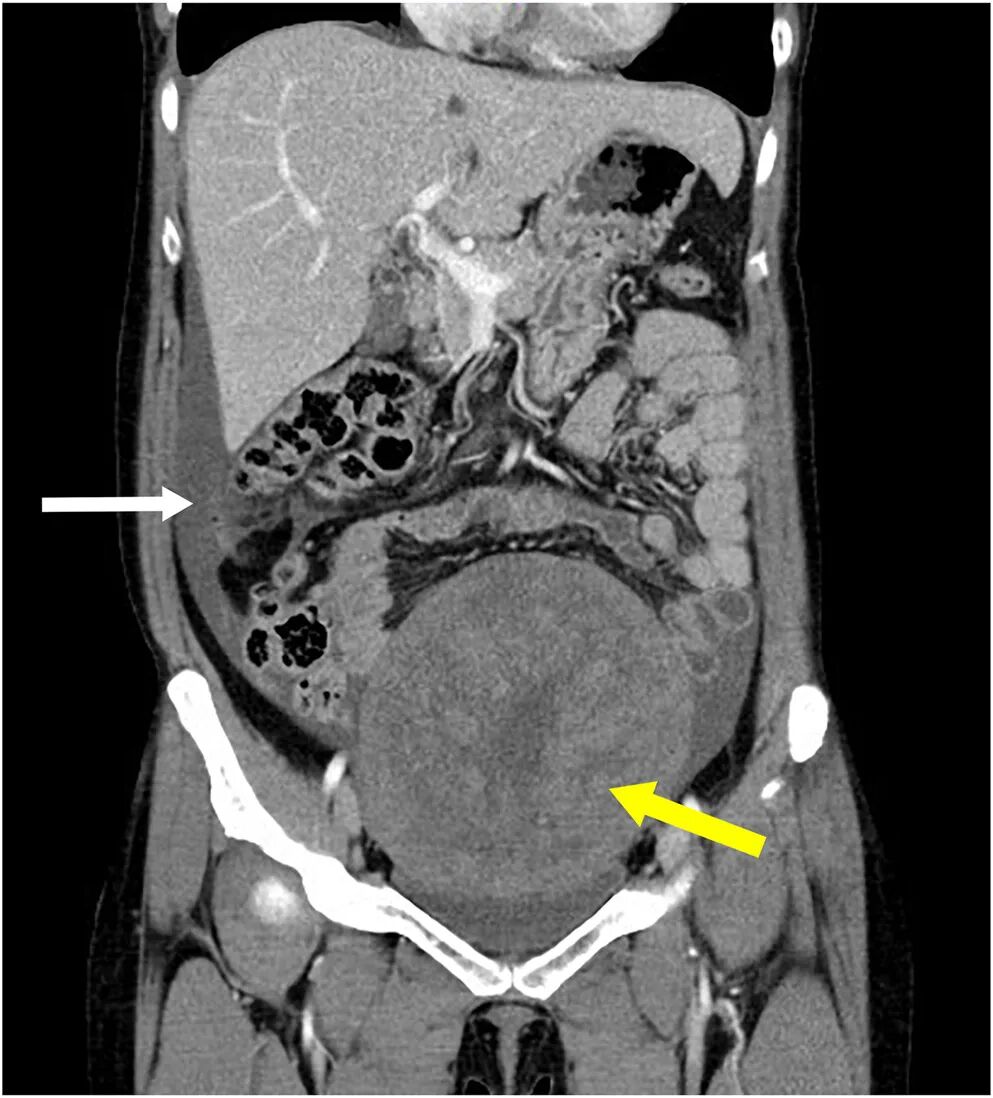

腹部计算机断层扫描(CT)显示盆腔内有一占位性病变,伴中等量腹水

及双侧胸腔积液

,且右侧较左侧更为明显(图2、图3)。

图2 腹部增强CT(冠状位)示盆腔内一巨大不均质肿瘤(黄色箭头)及腹水(白色箭头)。